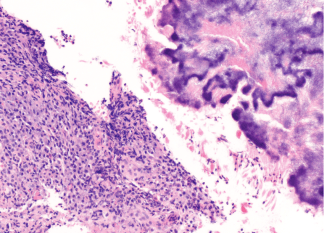

a) Hematoxylin-eosin staining: Sulfur granules seen. Dense acute and chronic lymphoplasmacytic inflammation with clusters of filamentous organisms

a) H&E stain b) Gram stain